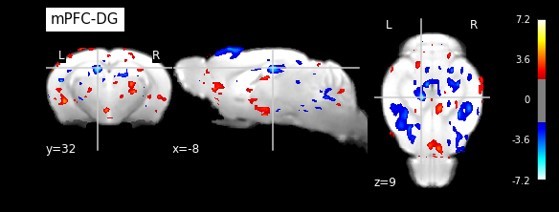

The researchers then teamed up with OIST’s former PhD student Dr. Hiroaki Hamada from the Neural Computational Unit. Through an MRI, they found that the connectivity between two key places regulating brain’s stress resilience was altered when the Tob gene was removed—the hippocampus and the pre-frontal cortex. From there, the researchers decided to look at the specific role that the gene plays within the hippocampus. They took mice without the Tob gene and injected this gene into the hippocampus, while leaving it nonexistent in other parts of the body. The level of fear and depression returned to normal, but the mice still had increased anxiety. The researchers then did the opposite—they created a mouse that had no Tob gene in the cells in the hippocampus but had it in the cells in the rest of the body. In this case, they found that the mice had normal levels of anxiety but increased fear and depression.